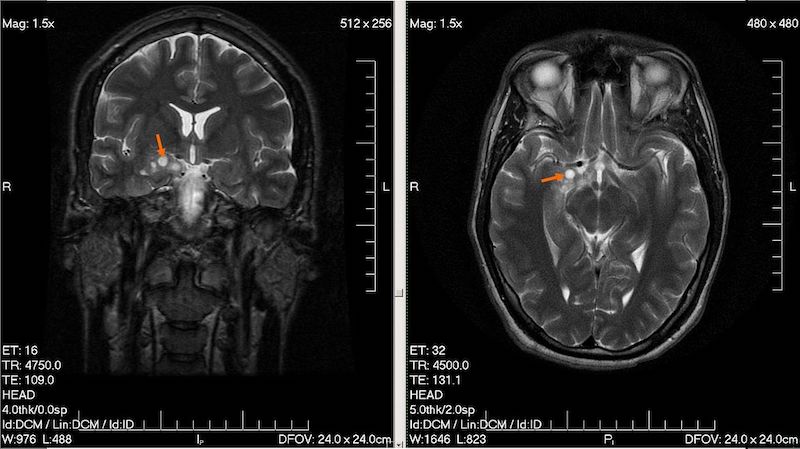

Wysokozróżnicowany glejak u 28-letniego mężczyzny Fot. Wikipedia

Na zdjęciu: Wysokozróżnicowany glejak u 28-letniego mężczyzny

Fot. Wikipedia

Dalsza diagnoza opiera się o badania obrazowe, czyli rezonans magnetyczny lub tomografię komputerową, na podstawie których rozpoznaje się guza mózgu. Są pewne cechy w obrazie diagnostycznym, które już na tym etapie pozwalają stwierdzić, że mamy do czynienia z glejakiem. Pewne rozpoznanie stawia się jednak dopiero na podstawie badania histopatologicznego, po usunięciu guza.